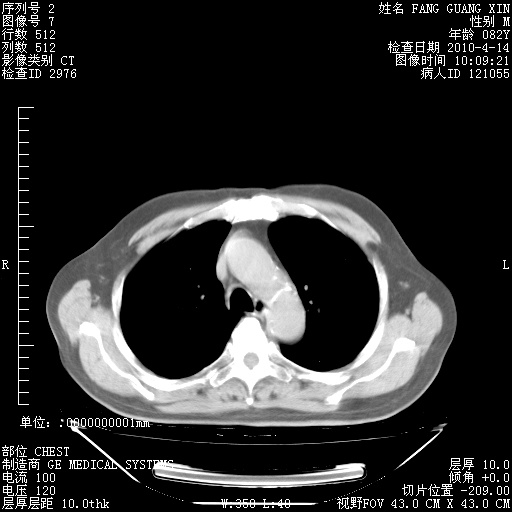

4月14日肺部CT